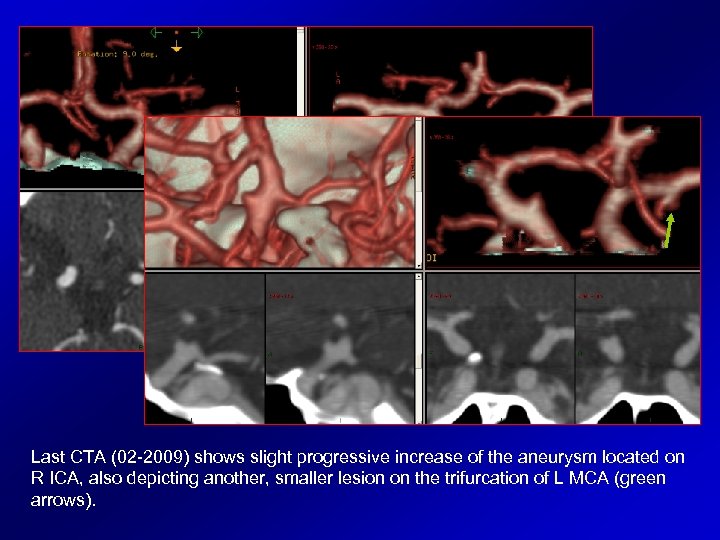

Last CTA (02 -2009) shows slight progressive increase of the aneurysm located on R ICA, also depicting another, smaller lesion on the trifurcation of L MCA (green arrows).

The retrospective review of first CTA (05 -2005) demonstrated the presence of the second de novo aneurysm, on the L MCA.